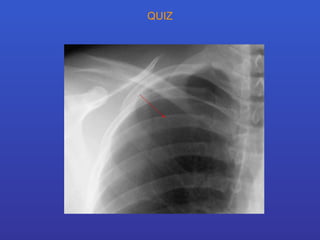

Contrôle positionnement cathéter central